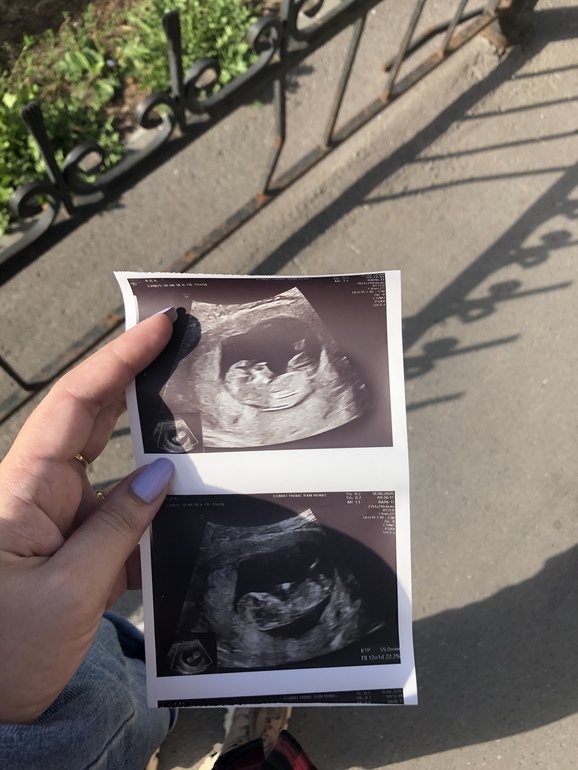

Погадаем над фото? 1 скрининг

Это мальчик) На второй черно -белой фотке четко виден Колокольчик вверх. У нас была точно такая же фотка

Мне кажется мальчик